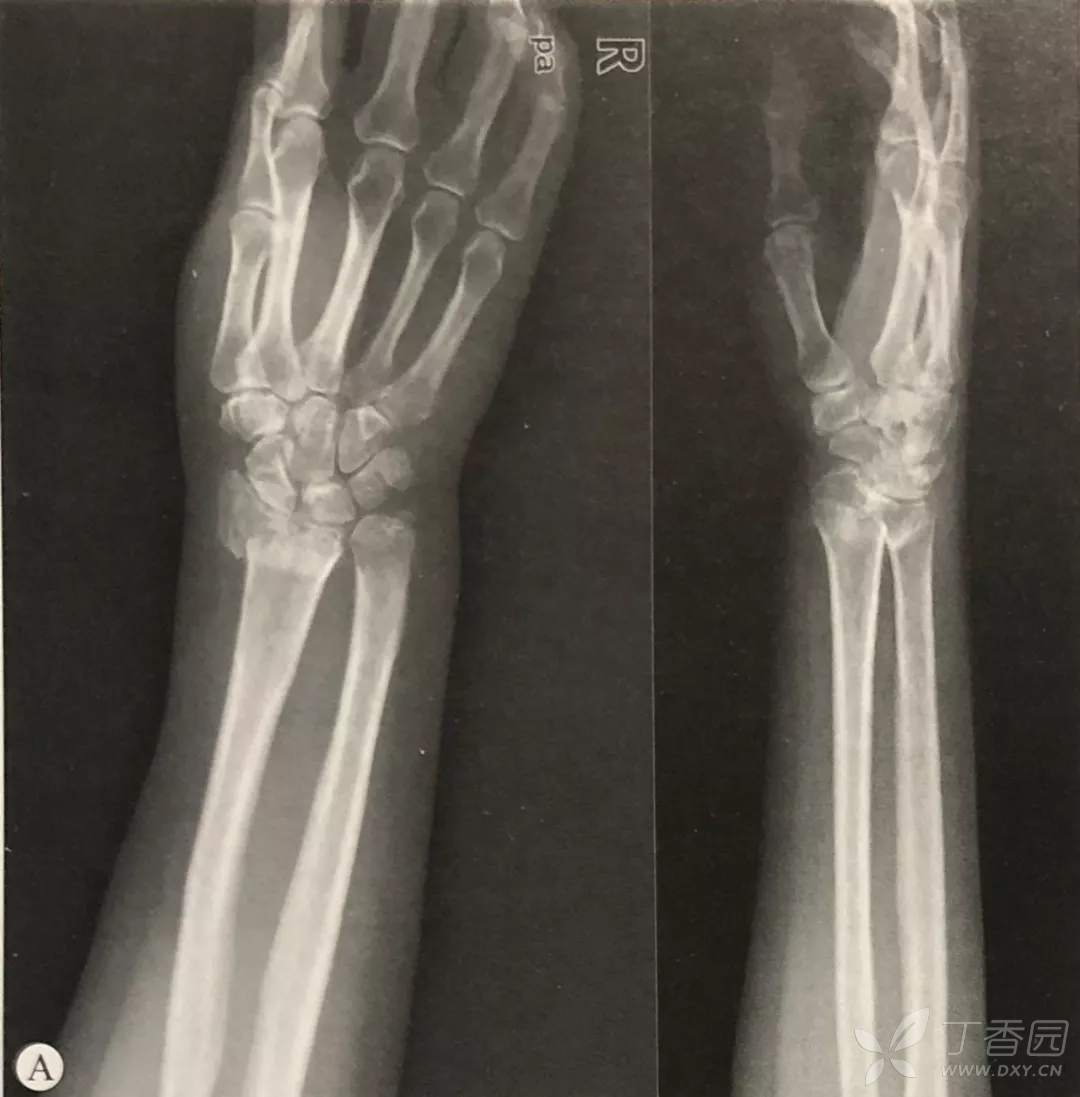

关节内骨折:

根据Melone分型,关节内骨折需要解决桡骨茎突、背侧唇、掌侧唇、冲床死骨以及尺骨远端骨折。